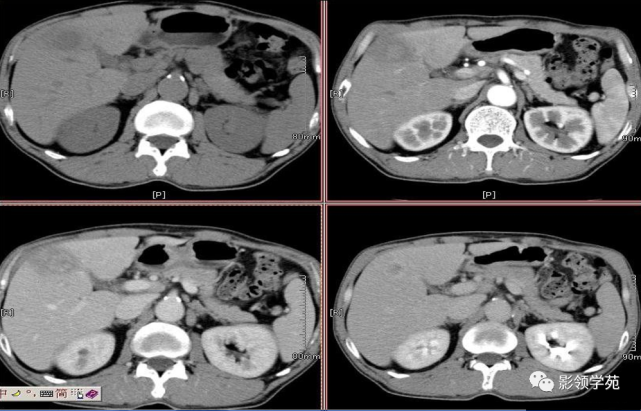

【专题综述】肝炎性假瘤的ct表现及病理分析

图片尺寸891x684

炎性假瘤(病灶形态不规则,边缘可呈刀切样,周围可见毛玻璃样改变,强化

图片尺寸820x704